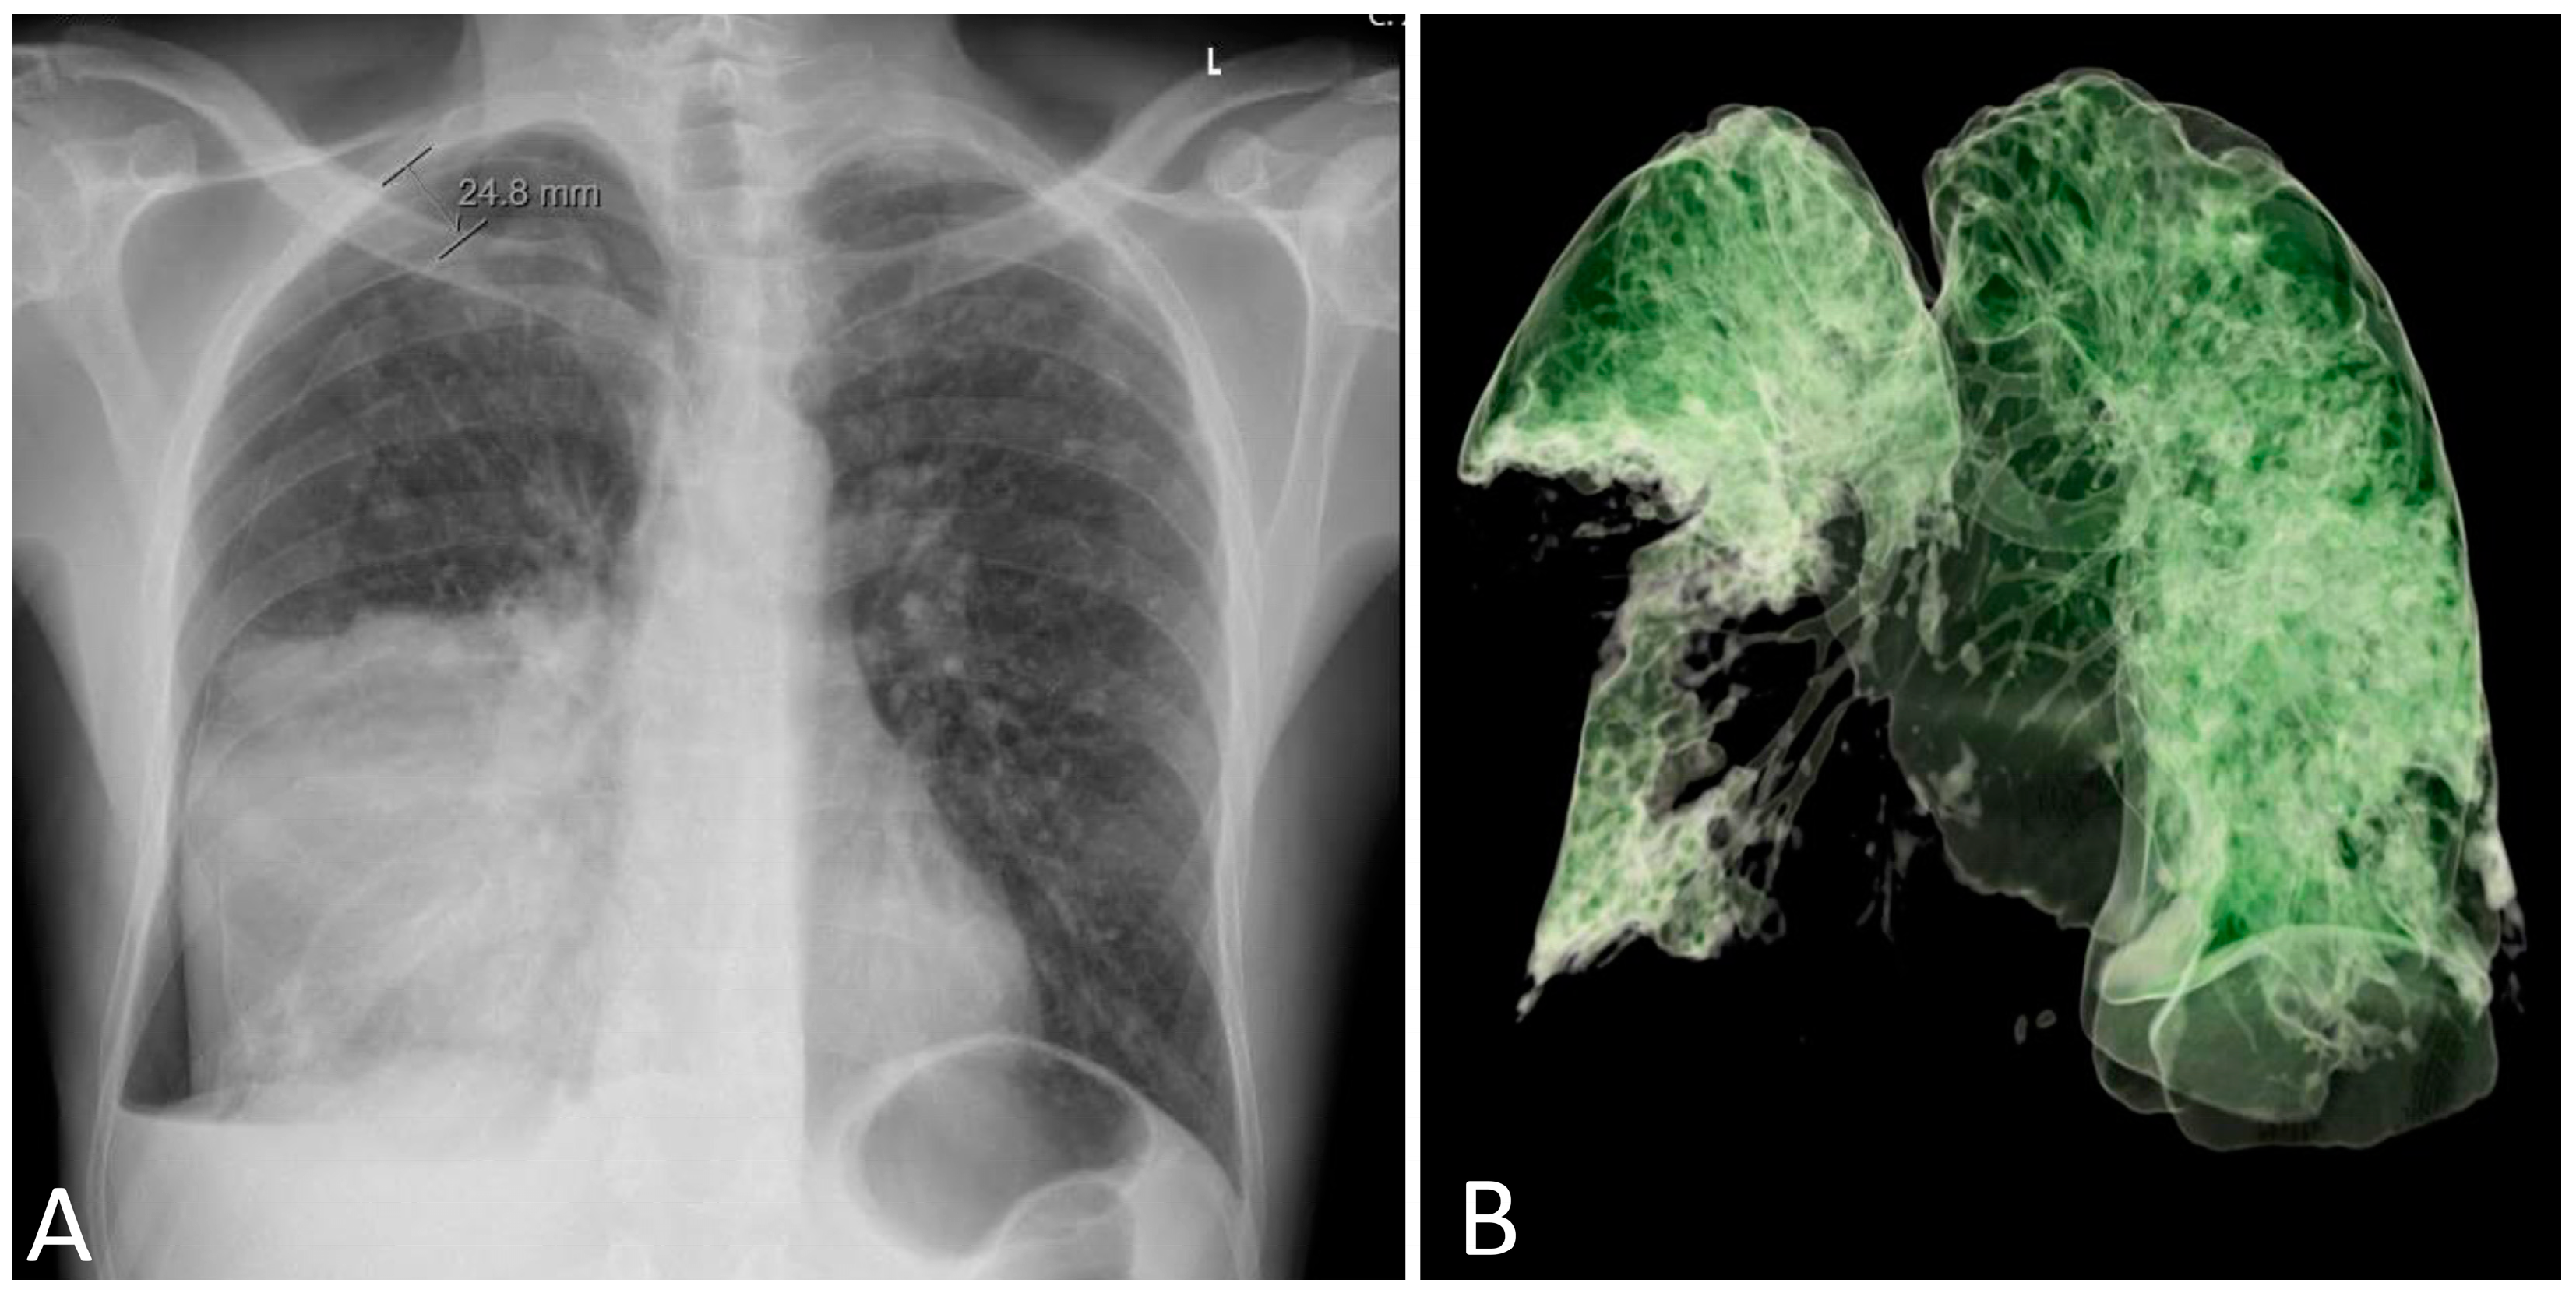

On admission, the patient was hemodynamically unstable, with an arterial blood pressure of 80/50 mmHg, a pulse of 125 beats/min, and tachypneic with a frequency of >40 breaths/minute with oxygen saturation of 45% on room air. The leukocyte count was 5.3 × 109/L, platelet count was 138 × 109/L, and C-reactive protein level was 523 mg/L (Supplemental File S1). Arterial blood gas (ABG) analysis with a fraction of inspired oxygen (FiO2) of 0.8 revealed a pH of 7.22, PaCO2 level of 7.22 kPa, PaO2 level of 6.8 kPa, and bicarbonate concentration of 19 mmol/L. His urine output was normal (300 mL/h). Early vasopressor therapy (noradrenaline 10–20 mL/h), oxygen therapy, and analgosedation with midazolam and fentanyl were initiated. The patient was intubated and mechanically ventilated with positive end-expiratory pressure (PEEP) of 10 cmH2O with a FiO2 of 0.6–0.8 in controlled mechanical ventilation (CMV) mode. Purulent secretions were drained from the thoracic drain. An emergency thoracic CT was performed (Figure 1B and Figure 2A) and revealed extensive right-sided pneumonia of the lower and middle lung lobes and a minimal effusion of 1 cm. After microbiology samples were taken, empirical broad-spectrum antimicrobial therapy consisting of cefepime (2 g every 12 h) and levofloxacin (500 mg every 12 h) was initiated. Due to severe hemodynamic instability, analgosedation was discontinued.

On day 8, due to the patient’s restlessness and inability to synchronize with the ventilator, a continuous infusion of dexmedetomidine was introduced, followed by a continuous infusion of midazolam and fentanyl due to extremely difficult ventilation with high oxygen concentrations and respiratory pressures (Paw greater than 30). In the intervals when interventions such as physical therapy and nursing interventions were performed, this asynchrony was significant. To optimize the patient’s care and comfort, he was relaxed using bolus doses of rocuronium. Between interventions, neuromuscular blockade was not required, and ventilation pressures were lower. A control CT of the thorax was performed, which revealed deterioration in terms of the progression of the inflammatory infiltrate to the right lung lobe (Figure 2B, Video S1). A thoracic surgeon was consulted several times.

On day 18, the patient was awake, conscious, oriented, and breathing spontaneously via face mask, and his SpO2 was 95% (Supplemental File S1). The patient’s clinical status and chest radiograph both improved, and the thoracic drain was removed. The same day after the drain was removed, SpO2 decreased with silent breathing sounds apically on the right lung. Pneumothorax was suspected and confirmed after a chest radiograph. Re-thoracentesis was performed (Figure 2C, Supplemental File S1).

Figure 2. Changes in the lung window of CT in a 53-year-old shipyard worker after severe chest trauma with V/Q mismatch and respiratory failure requiring mechanical ventilation: on admission (A), after 6 days when pneumonia also developed on the left side (B), and after Stenotrophomonas maltophilia was identified and treated with sulfamethoxazole/trimethoprim, a regression of lung infiltrates was observed (C).